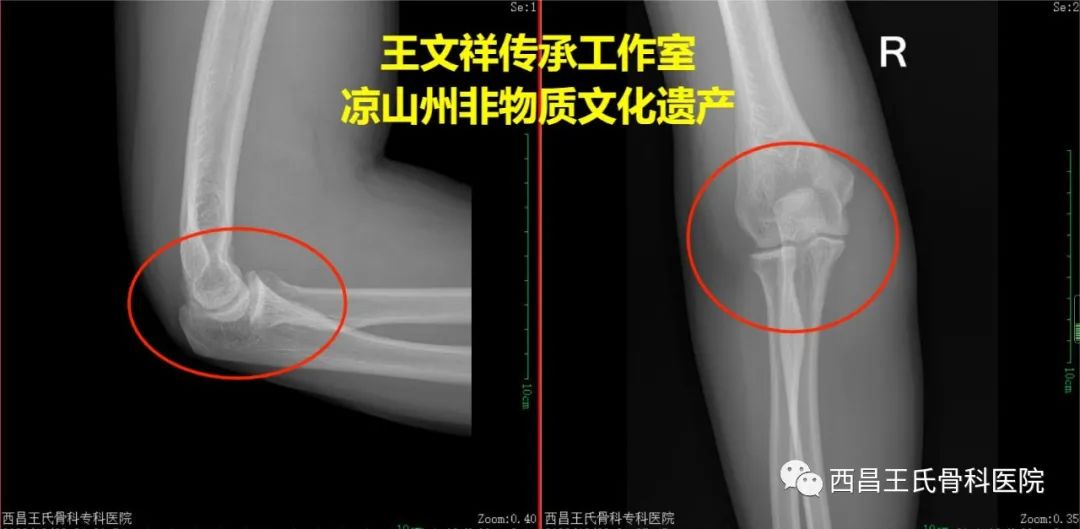

手法复位病例一:肘关节脱位

复位前

复位后